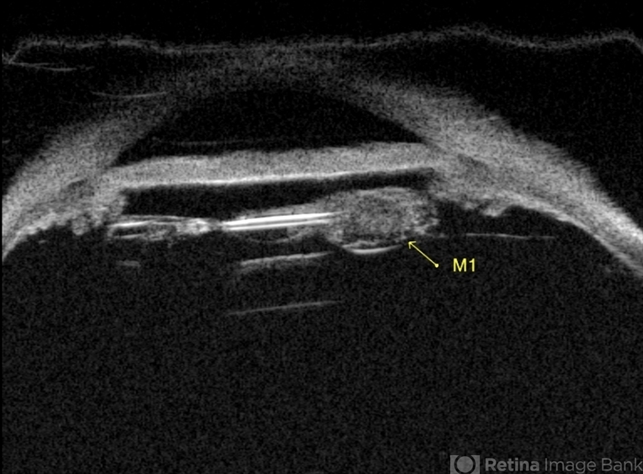

- Lacteocrumenasia, ultrasound biomicroscopy

- Gustavo U. Fonseca Aguirre, Hospital Conde de Valenciana, Ciudad de México

- Imaging device

- Ultrasonography device

- A 75-year-old female with a history of cataract surgery with intraocular lens implantation 20 years ago presented with progressive visual loss. On slit lamp examination, opaque material was found in the capsular bag behind the intraocular lens. Ultrasound biomicroscopy revealed hyperechoic material contained in the temporal-posterior sector of the capsular bag corresponding to lacteocrumenasia.